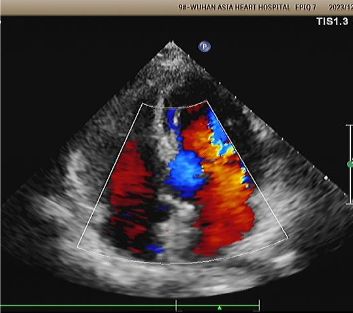

Diagnosis: Positive bubble study.

Implant: 2424 MemoSorb® biodegradable PFO occluder deployed under echo and DSA guidance.

Day 1 to 9 Months:

No residual shunt observed.